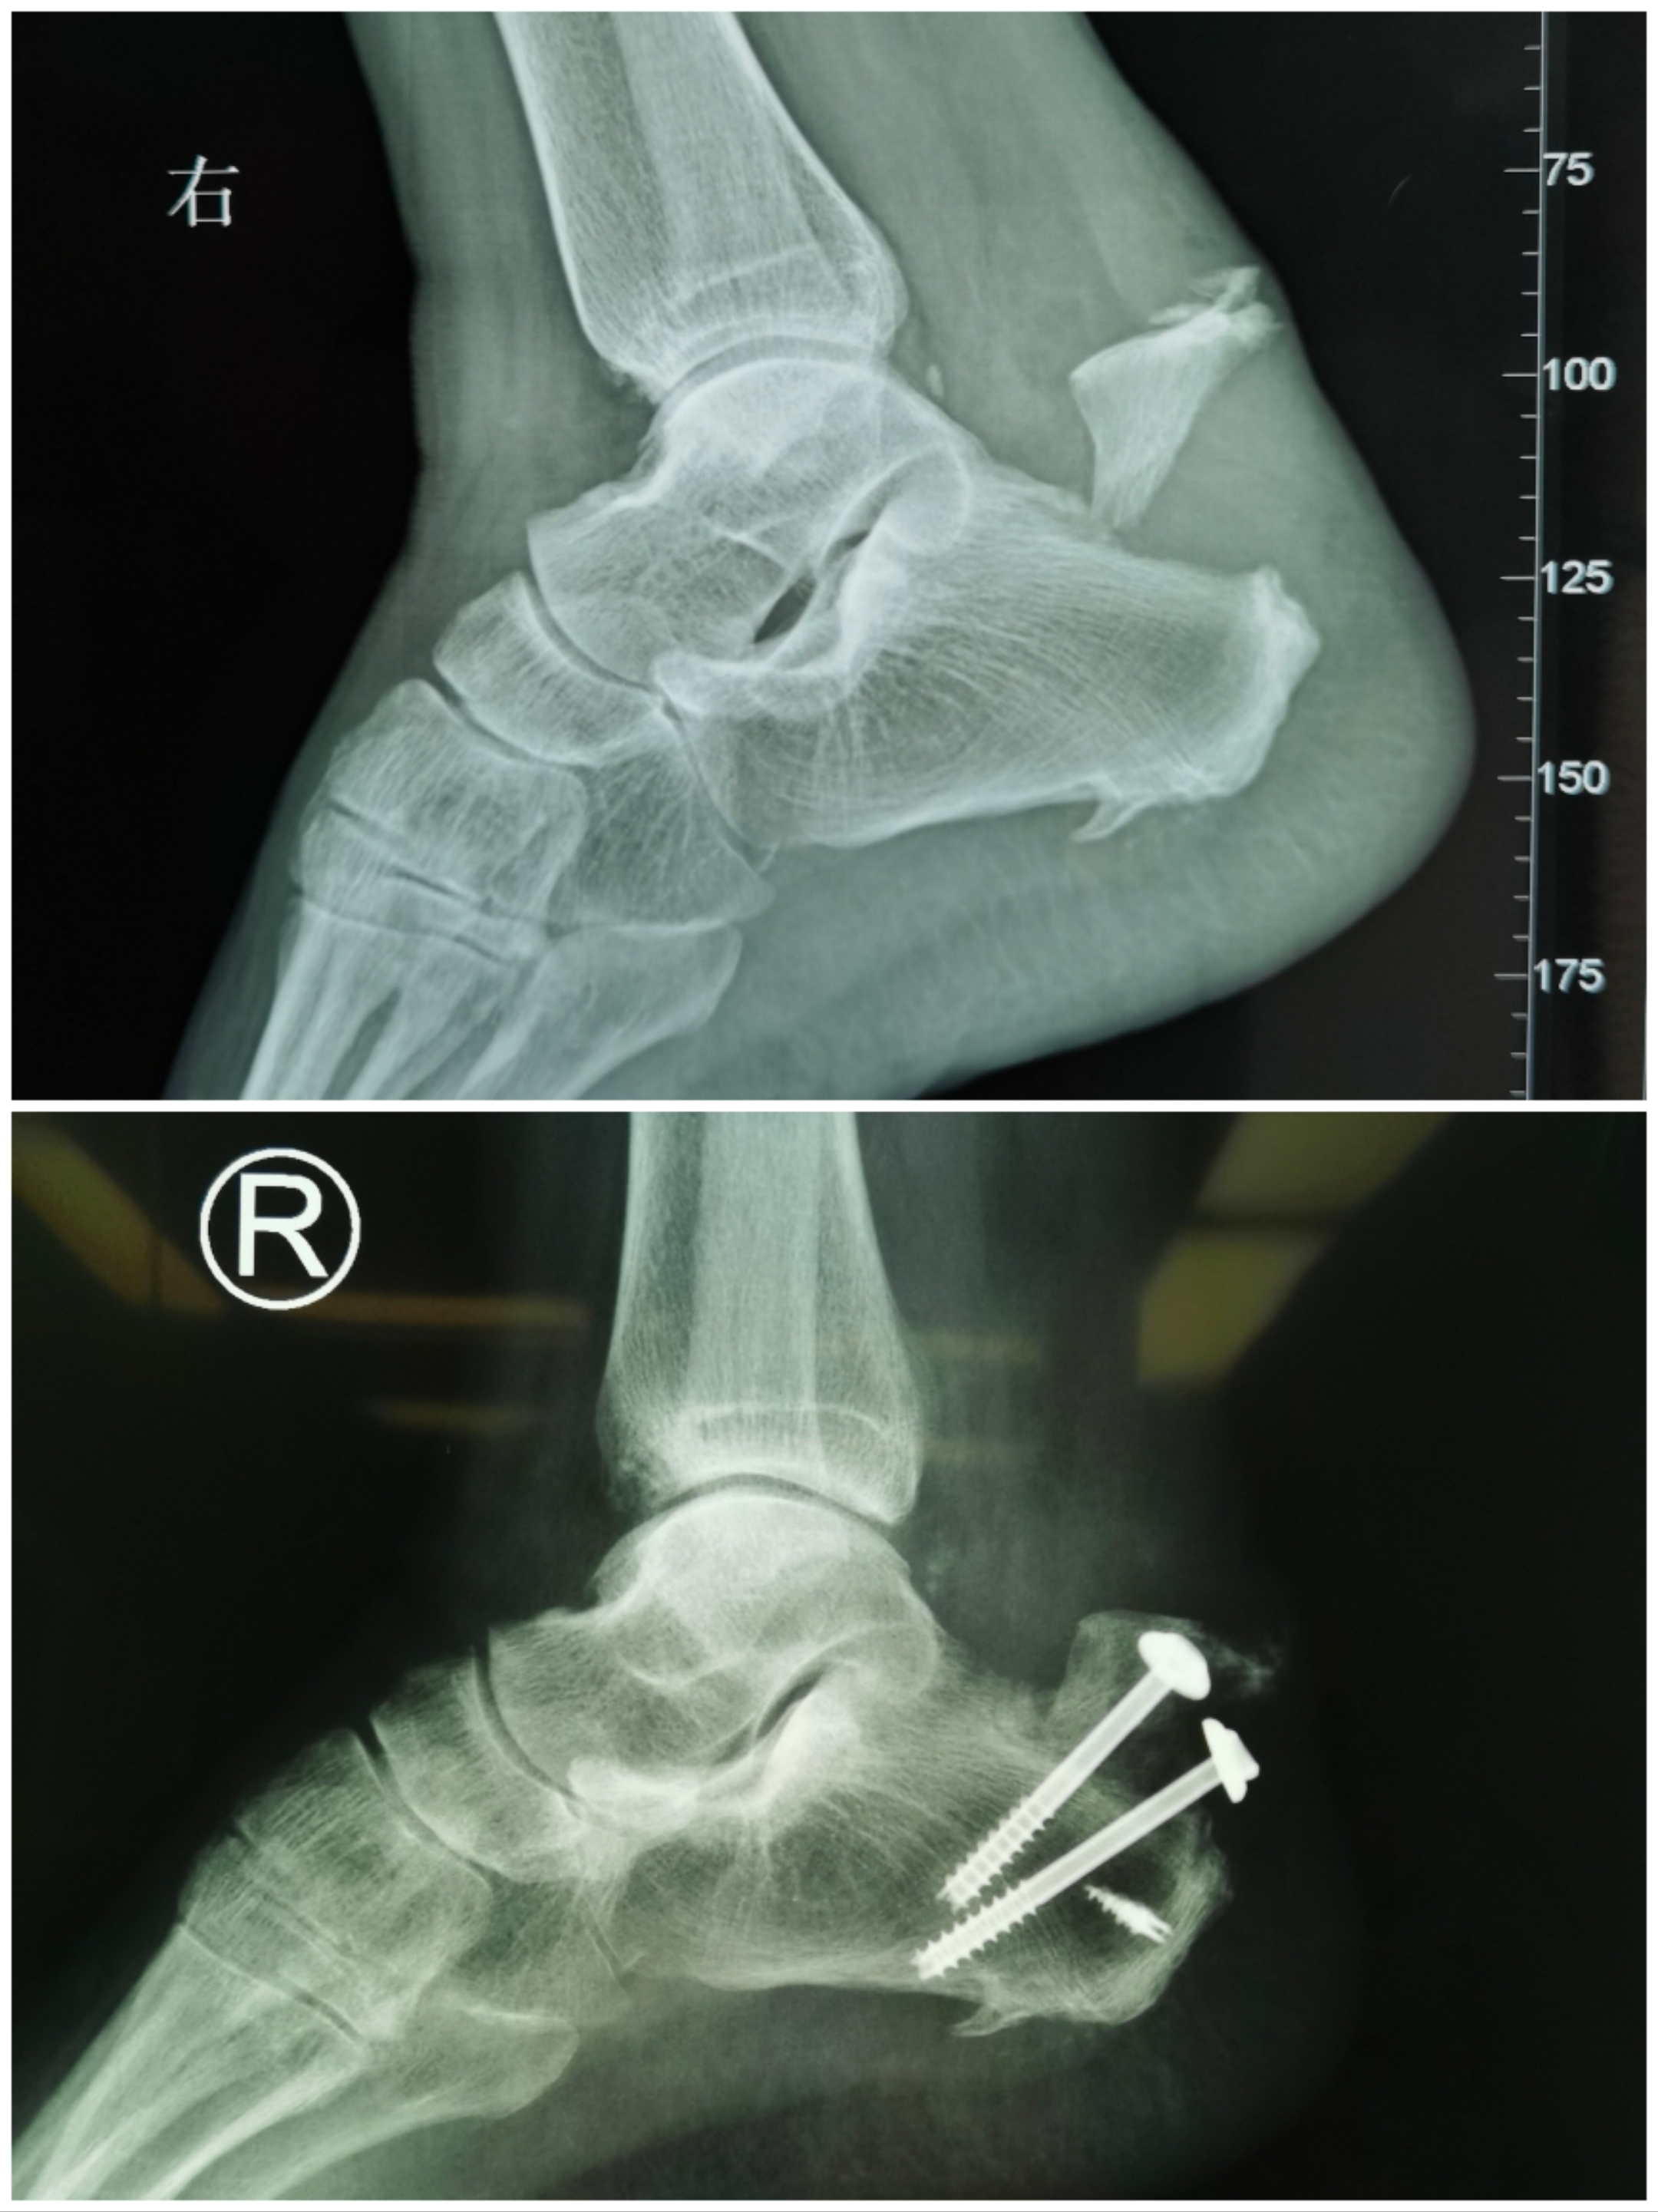

一、基礎(chǔ)知識(shí)1、跟骨關(guān)節(jié)面解剖前、中關(guān)節(jié)面融為一體,與后關(guān)節(jié)面間有骨竇相隔。后關(guān)節(jié)面承載人體45%的重量。跟骨前內(nèi)側(cè)有載距突,為螺絲釘固定承力之處。外側(cè)面跖側(cè)面2、X片測(cè)量:跟骨的解剖學(xué)標(biāo)志最重要的就是兩個(gè)角度:1)Bohler角25~40°;2)Gissnae角120~145°。3、影像學(xué)檢查1)X片檢查:踝關(guān)節(jié)正位、側(cè)位、踝穴位、跟骨軸位;足前后位、側(cè)位、斜位;評(píng)估踝關(guān)節(jié)、距骨、跟骨、距下關(guān)節(jié)、跟骰關(guān)節(jié)、跟骨內(nèi)側(cè)壁情況。2)CT:平行于足底的平面和垂直于距骨后關(guān)節(jié)面的平面進(jìn)行2?3mm層距的掃描。4、分型:1)Essex-Lopresti分型,無移位、舌形塌陷、后關(guān)節(jié)面塌陷、粉碎型。2)Sander分型:CT分型:骨折線自外向內(nèi)描述為ABC型。1型關(guān)節(jié)外骨折;2型一條骨折線;3型兩條骨折線;4型三條以上骨折線。二、治療原則1、準(zhǔn)確復(fù)位關(guān)節(jié)面;2、恢復(fù)跟骨的整體幾何外形和長(zhǎng)寬高;3、恢復(fù)距下關(guān)節(jié)面的平整和三個(gè)關(guān)節(jié)面之間的正常解剖關(guān)系;4、恢復(fù)G、B角和后足的負(fù)重力線,外翻0~5°;三、手術(shù)適應(yīng)證1、移位明顯,不穩(wěn)定的跟骨骨折。2、關(guān)節(jié)塌陷型。3、SandersⅡ、Ⅲ及仍可復(fù)位重建后關(guān)節(jié)面的SandersⅣ型跟骨骨折或保守治療失敗的患者。四、手術(shù)中C-B使用技巧1、跟骨軸位球管位于小腿后側(cè),踝被伸,足踏于接受器。球管-接受器與小腿縱軸在同一水平面上。2、跟骨側(cè)位五、手術(shù)流程1、體位及術(shù)前準(zhǔn)備創(chuàng)傷后通常在12~24h內(nèi)手術(shù)較為適宜,或傷后7~10天腫脹消退皮膚皺褶出現(xiàn)為手術(shù)時(shí)機(jī)。全麻、硬膜外麻醉、神經(jīng)阻滯麻醉。側(cè)臥位,骨突部墊軟墊保護(hù),患肢在后,健側(cè)在前?;紓?cè)大腿根部上止血帶。2、切口(第一步)外側(cè)擴(kuò)大L形入路(ELA)由于手術(shù)暴露廣泛、骨折復(fù)位操縱方便而一直是跟骨骨折ORIF的金標(biāo)準(zhǔn)。1)L切口,起于外踝尖后上3cm,腓骨后緣與跟腱之間向下,外踝與足跟中點(diǎn),至跟骨下方轉(zhuǎn)90度向前,沿足底跖側(cè)皮膚與外側(cè)皮膚之間切開(足背正常皮膚與增厚的跖底皮膚交界處)到遠(yuǎn)端呈弧形向背側(cè)延伸3cm,至第五跖骨基底近端1cm處。L形夾角盡量大些。近端切口剪開,防止傷及腓腸神經(jīng)。跟骨結(jié)節(jié)處開始切開皮膚皮下直達(dá)骨膜,向前上方掀起:骨膜、踝關(guān)節(jié)韌帶、腓骨長(zhǎng)短肌、皮神經(jīng)、皮瓣,形成全厚骨膜皮瓣。(用刀片以幾乎與跟骨外側(cè)面平行的方向進(jìn)行銳性剝離)。充分解剖達(dá)跟骨結(jié)節(jié)、距下關(guān)節(jié)、跟骰關(guān)節(jié),去除距骨竇脂肪墊,暴露跟骨后關(guān)節(jié)面及跟骨全部外側(cè)壁。(注:注意腓腸神經(jīng)跟腓韌帶距跟關(guān)節(jié)囊與腓骨肌腱鞘的修復(fù)與保護(hù)!)2)使用No-touch(不接觸)技術(shù)用數(shù)枚克針分別釘于距骨后關(guān)節(jié)面打入1根(腓骨和腓骨肌腱后側(cè)的距骨體),距骨頂部打入1根,距骨頸1根,骰骨1根,腓骨下端牽開軟組織與骨膜皮瓣。避免使用拉鉤顯露,反復(fù)調(diào)整拉鉤位置并大力牽引有可能進(jìn)一步破壞皮瓣血供。3、整復(fù)先恢復(fù)三維長(zhǎng)寬高整體解剖,即跟骨高度、長(zhǎng)度、寬度,然后再恢復(fù)關(guān)節(jié)面。1)手法復(fù)位(第二步)?大巾鉗置于跟骨結(jié)節(jié)上方,向下后牽引跟腱恢復(fù)跟骨高度、長(zhǎng)度,恢復(fù)跟骨前部的完整性,包括前關(guān)節(jié)面和中關(guān)節(jié)面,跟骰關(guān)節(jié)和跗骨竇。?同時(shí)跖屈前足,用雙拇指由足底向足背推擠跟骨前部,術(shù)者則配合用力向跖側(cè)方向牽拉足跟后部,此種折頂力可恢復(fù)貝累角。?然后用雙手掌緊握足跟,向中心擠壓跟骨,類似擠扁空蛋殼的感覺,恢復(fù)跟骨寬度。?同時(shí)注意矯正跟骨內(nèi)翻,恢復(fù)0°~5°外翻角。?手法為:1.軸向牽開;2.糾正內(nèi)翻;3.恢復(fù)高度;4.中心擠壓。2)撬撥復(fù)位(第三步)掀起菲薄之跟骨外側(cè)皮質(zhì)(蒂在足底或后側(cè),可以起到復(fù)位時(shí)參照的作用),觀察距下關(guān)節(jié)面的塌陷、翻轉(zhuǎn)及內(nèi)側(cè)壁的移位情況。以距骨關(guān)節(jié)面為模板,骨鑿放入骨折線內(nèi)撬撥恢復(fù)后關(guān)節(jié)面形態(tài),從內(nèi)至外、從前向后復(fù)位后關(guān)節(jié)面的內(nèi)、中、外骨折塊,關(guān)節(jié)面下5mm,冠狀面克針或螺釘固定。3)復(fù)位標(biāo)識(shí)?Gissane角是十分重要的解剖標(biāo)志,其由跟骨前后關(guān)節(jié)面外側(cè)延伸并和跟骨體外側(cè)共同構(gòu)成。它對(duì)于骨折的復(fù)位有很好的指示作用:跟骨的后關(guān)節(jié)面必須復(fù)位到這個(gè)骨性標(biāo)志。?再次植入翻開的跟骨外側(cè)壁皮質(zhì)部分,這可作為“鑰匙”,用以評(píng)估和確保合適的復(fù)位和恢復(fù)跟骨高度。4、固定1)跟距固定(第四步)通過C型臂X線機(jī)透視觀察跟骨高度、長(zhǎng)度及后關(guān)節(jié)面復(fù)位滿意,B氏角、G氏角正常。用2枚直徑為2.0mm的克氏針自跟骨結(jié)節(jié)下方平行置入,克氏針穿過骨折線和跟骨關(guān)節(jié)面到達(dá)距骨以維持復(fù)位。2)鎖釘跟骨板固定(第五步)三點(diǎn)固定原理:跟骨結(jié)節(jié),跟骨前突,跟骨后關(guān)節(jié)面(即跟腱止點(diǎn)附近的軟骨下骨、跟骰關(guān)節(jié)面的軟骨下骨、載距突的致密骨)。注意板的方向,三角尖向上,底向下。?放置鎖定跟骨鋼板克針臨時(shí)固定?術(shù)中C-B檢查確認(rèn)鋼板置于合適位置。?置入螺釘?固定載距突(第六步)跟骨后關(guān)節(jié)面與中關(guān)節(jié)面交界處(G角頂點(diǎn)),關(guān)節(jié)面下5mm,向內(nèi)側(cè)遠(yuǎn)端傾斜15度進(jìn)針,拉力釘固定于載距突。(即G角處下緣進(jìn)釘)?保護(hù)內(nèi)側(cè)血管神經(jīng)肌腱5、植骨(第七步)1)對(duì)于嚴(yán)重的關(guān)節(jié)面壓縮骨折、骨質(zhì)缺損的患者,在跟骨板固定前可用自體髂骨塊或人工骨、同種異體骨填充,然后回蓋跟骨外側(cè)壁。2)在放跟骨板之前,用擊錘錘擊跟骨外側(cè)壁,恢復(fù)跟骨寬度;它帶來的額外好處是,跟骨體部的骨質(zhì)缺損間隙消失,而不必植骨。如果一定要植骨,可以劈開髂骨,保留內(nèi)外板,只取板障內(nèi)的松質(zhì)骨,從而減少植骨量。6、閉合切口(第八步)1)解脫止血帶,側(cè)底止血,修復(fù)腓骨肌腱鞘與跟腓韌帶。2)放置引流管,注意引流管端應(yīng)該置于跟骨外側(cè),L形皮瓣下方,避免皮瓣下積液導(dǎo)致皮瓣漂浮、壞死。3)皮膚縫合?縫合方法建議采用allgower縫合,對(duì)皮膚血供破壞少。?張力比較大的傷口分兩層縫合皮下組織應(yīng)用可吸收縫線縫合,自垂直和水平切口的兩端開始向中間間斷縫合,此時(shí)先不打結(jié),可以通過調(diào)整針距使L型皮瓣頂角皮下無張力,自兩邊至皮瓣頂角,完成所有縫合后自兩端向中央順次打結(jié),這樣可保證每一針縫的結(jié)實(shí)。然后再用不可吸收線或皮釘閉合切口。六、術(shù)后處理與功能鍛煉1、術(shù)后處理:1)厚棉墊、彈力綁帶加壓包扎;石膏功能位固定;抬高患肢、靜脈使用抗生素及抗凝治療。2)術(shù)后前3天每日換藥,一般48小時(shí)后拔負(fù)壓引流。3)術(shù)后第2天即可進(jìn)行足趾活動(dòng),踝泵訓(xùn)練;1周左右可進(jìn)行踝關(guān)節(jié)屈伸功能鍛煉;術(shù)后3周拆線,糖尿病或營(yíng)養(yǎng)狀況不佳患者可適當(dāng)延期。4)2周后患肢可下地不負(fù)重功能鍛煉;手術(shù)后6~8周部分負(fù)重(體重1/4),手術(shù)后12周完全負(fù)重。2、術(shù)后功能鍛煉1)術(shù)后第一天跟骨骨折的康復(fù)鍛煉可行足趾關(guān)節(jié)等張運(yùn)動(dòng),下肢肌肉等張靜力性收縮,每天3~4次每次15~30分鐘。隨時(shí)間延長(zhǎng),可適當(dāng)增加運(yùn)動(dòng)量。2)術(shù)后2周開始滾酒瓶功能鍛煉,坐位將一玻璃瓶橫放在地上,腳踩在玻璃瓶上,來回滾動(dòng),踝關(guān)節(jié)隨之做屈伸活動(dòng)。逐漸加大踝關(guān)節(jié)屈伸度數(shù),瓶子滾到腳尖部位時(shí)腳跟要著地,瓶子滾到腳跟時(shí)腳尖要著地。3)術(shù)后4~6周,可行踝關(guān)節(jié)被動(dòng)跖曲、背伸運(yùn)動(dòng),禁止內(nèi)外翻運(yùn)動(dòng)。同時(shí)配合中藥熏洗泡腳。4)術(shù)后6~8周跟骨骨折康復(fù)訓(xùn)練可逐漸負(fù)重訓(xùn)練。5)術(shù)后8~12周跟骨骨折康復(fù)訓(xùn)練可行踝關(guān)節(jié)主動(dòng)運(yùn)動(dòng)訓(xùn)練,術(shù)后12周跟骨骨折康復(fù)訓(xùn)練可行步態(tài)訓(xùn)練。6)中藥熏洗外用:艾條(葉)、桑枝、赤芍、秦艽、防風(fēng)、透骨草各30骨,5副,每副用3天。每次熏洗20~30分鐘,溫度40度。七、Maryland足功能評(píng)分標(biāo)準(zhǔn)說明:Maryland足功能評(píng)分,由Sanders于1993年在評(píng)價(jià)關(guān)節(jié)內(nèi)跟骨骨折的手術(shù)療效時(shí)提出的,主要用于對(duì)足和踝關(guān)節(jié)損傷后的疼痛、功能、外觀及活動(dòng)度進(jìn)行客觀評(píng)價(jià)。該評(píng)分滿分為100分,其中疼痛占45分,功能評(píng)價(jià)占55分,包括步態(tài)、行走距離、穩(wěn)定性、支撐工具、跛行、穿鞋、上樓梯及行走時(shí)對(duì)地面的要求,外觀和活動(dòng)度分別占10分和5分。評(píng)定標(biāo)準(zhǔn):優(yōu)90-100分;良75-89分;中50-74分;差<50分。八、臨床病例1.xxx女53歲右跟骨粉碎骨折2016.12.122、xxx男26歲左跟骨骨折2017.8.313、xxx男35歲右跟骨骨折2017.11.234、xxx男49歲右跟骨骨折2024年11月11日九、小結(jié)跟骨骨折發(fā)病率逐年增加,精準(zhǔn)處理降低傷殘率至為重要,包括:1、手術(shù)時(shí)機(jī);2、切口顯露;3、整復(fù)手法與骨折復(fù)位順序技巧,尤其是關(guān)節(jié)面的復(fù)位。4、內(nèi)固定順序與技巧,尤其是載距突固定手法。5、切口閉合方法與選擇。6、手術(shù)后處理與康復(fù)。7、Maryland足功能評(píng)分標(biāo)準(zhǔn)本組病例全部達(dá)到良好以上。山西醫(yī)科大學(xué)第二醫(yī)院骨顯微手外科醫(yī)療團(tuán)隊(duì)2024年11月17日于太原聯(lián)系方式山西醫(yī)科大學(xué)第二醫(yī)院骨顯微手外科特需骨科門診地點(diǎn):山大二院體檢中心二樓特需骨科門診時(shí)間:周一下午(梁炳生主任醫(yī)師)專家門診地點(diǎn):山大二院門診南1層骨科1017診室專家門診時(shí)間:周二上午(梁炳生主任醫(yī)師)預(yù)約掛號(hào):“健康山西網(wǎng)”預(yù)約掛號(hào)預(yù)約加號(hào):“好大夫網(wǎng)”預(yù)約加號(hào)病房地點(diǎn):山大二院住院部3號(hào)樓7層病區(qū)病房電話:0351-3365107文章部分內(nèi)容來源于網(wǎng)絡(luò),如有侵權(quán)請(qǐng)聯(lián)系作者刪除。